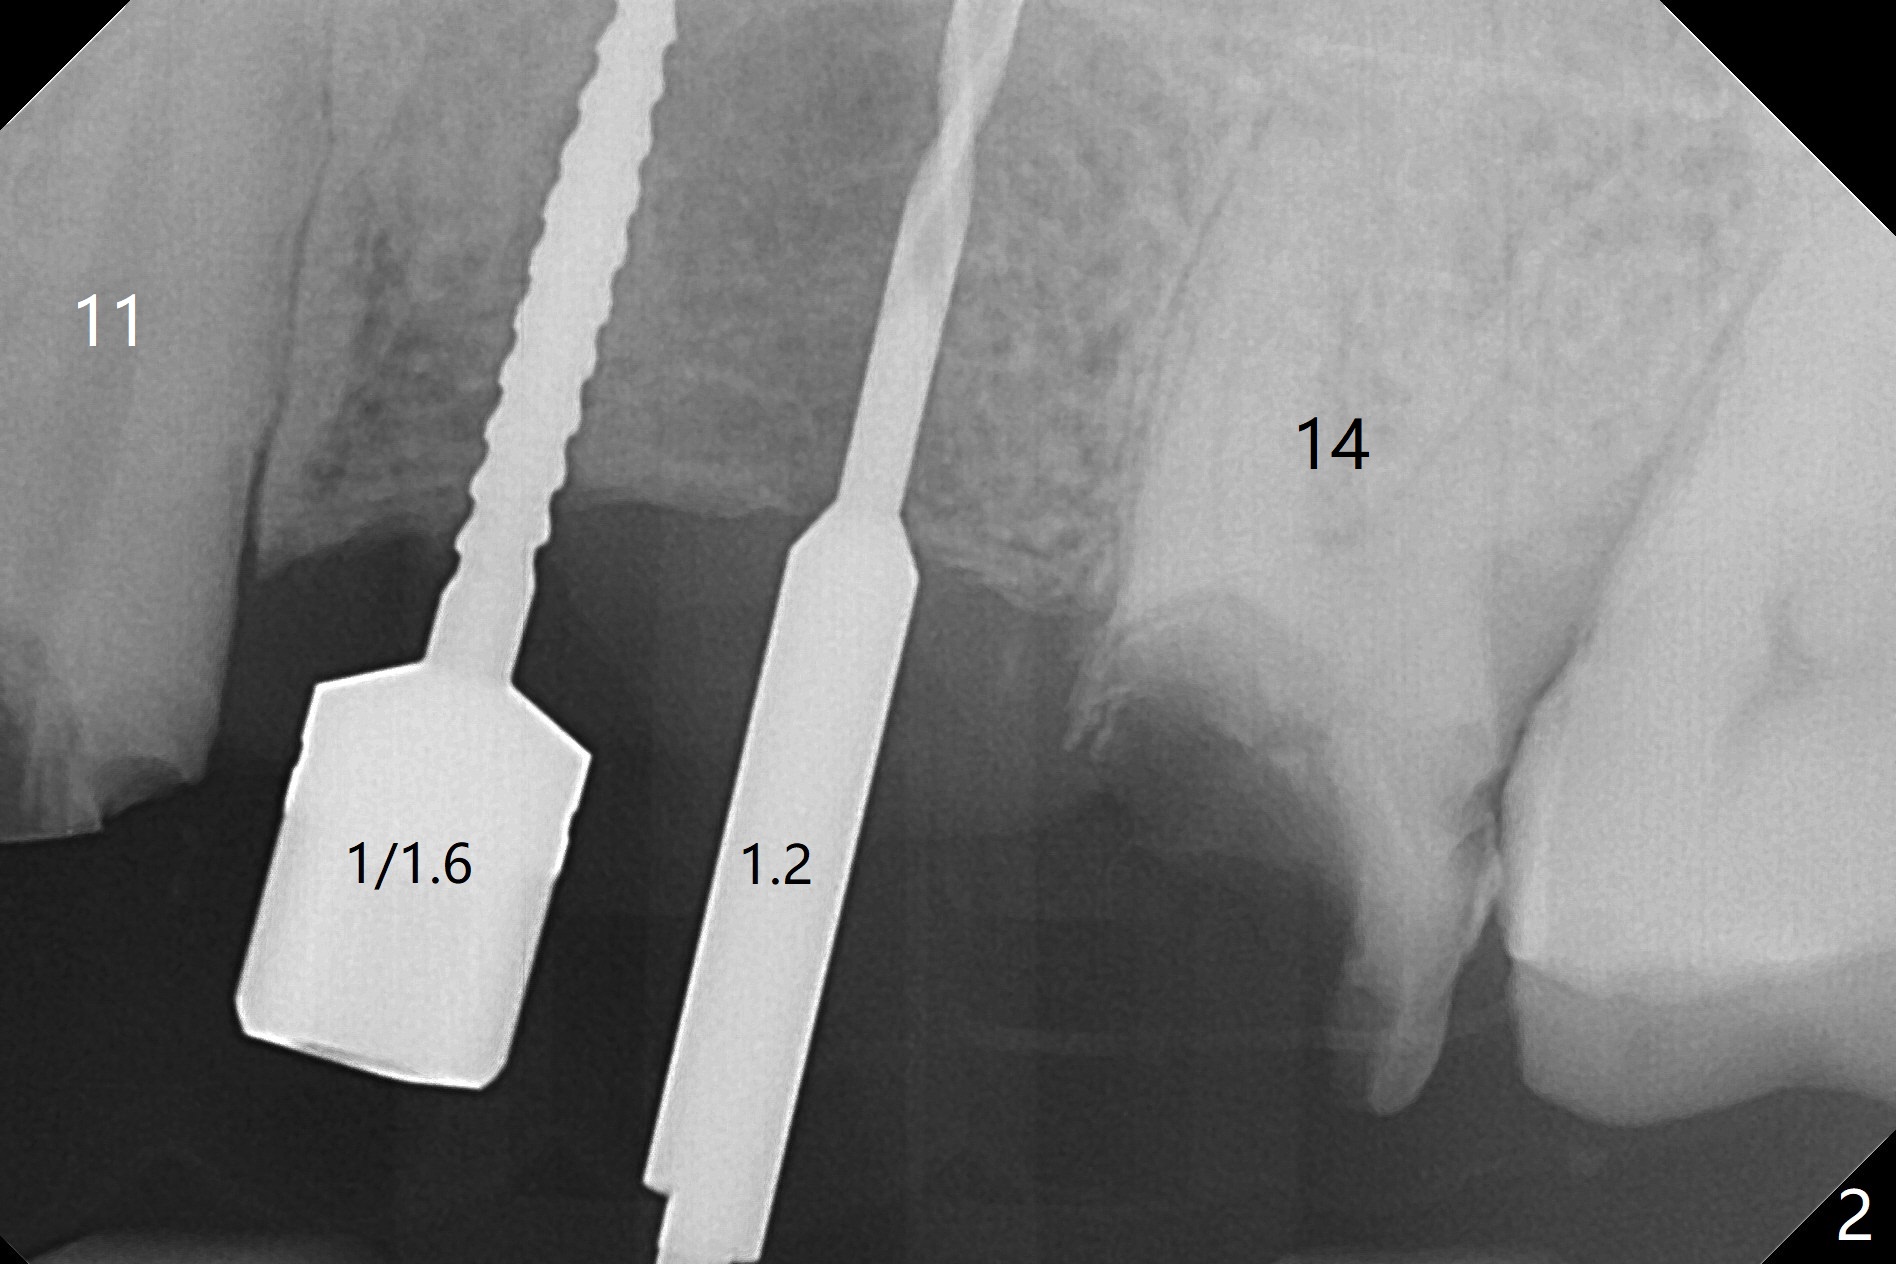

The edentulous ridge is narrow between the residual roots of #11 and 14 (Fig.1). Since the bone density is low in the edentulous area, DIO bone expanders are used (e.g., #1 (1/1.6 mm) Fig.2) after 1.2 mm initial drill. A 2x14(2) mm 1-piece implant is placed at #12 with 4 mm ridge width, while a 3x10 (2) mm dummy implant is partially placed after use of Bone Expander #2 (1.3/2.3 mm). The latter is replaced by a definitive one (3x12(2) mm), while the one at #12 is placed deeper (Fig.4). After extraction and placement of PRF and Vanilla Graft for sinus lift (Fig.4 black *), a 5x10 mm 2-piece implant is placed at #14, while a dummy implant is placed at #11 (Fig.4,5). As the osteotomy at #11 is 4.9 mm longer than the dummy (Fig.5), a definitive one is 3 mm longer (Fig.6). Osteogen plug is placed in the apical portion of each socket at #11 and 14, while Vanilla and Osteogen are packed in the coronal portion of the socket (Fig.4,6 *). Although primary stability of each implant is not high (30/40 Ncm), splinted provisional with occlusal clearance seems to be sufficient for implant osteointegration. There is no discomfort 9 days postop (Fig.7). Impression is taken 3 months postop, since he plans to return to home country for business (Fig.8). Single unit crowns are cemented 4 months postop (Fig.9,10). The abutment screw at #14 needs retightening 6 months post cementation. The access hole slightly buccal. Chewing pain at #12 is reduced after occlusal adjustment 6.5 months post cementation (Fig.11).